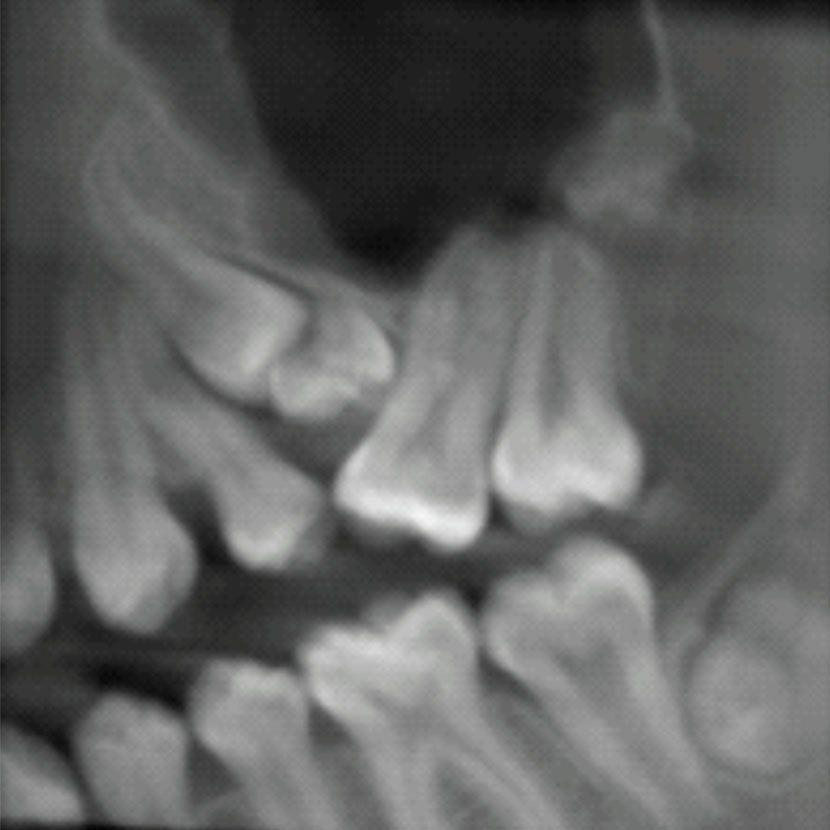

En algunos casos puede ser necesario extraer las llamadas “muelas del juicio” o tercer molar, en otros, puede ser necesaria la extracción de otras piezas tales como premolares o incisivos, lo cual dependerá de las particularidades del caso clínico.

El procedimiento quirúrgico como tal va a depender de la complejidad de la pieza dental en particular, si esta se encuentra sana y correctamente posicionada en boca, el procedimiento será sencillo y corto, sin embargo si la pieza dental se encuentra en una posición anómala y/o cubierta por hueso, la extracción puede complejizarse un poco más pudiendo ser necesaria la utilización de instrumental rotatorio para poder retirar el hueso que cubre al diente y acceder a él.